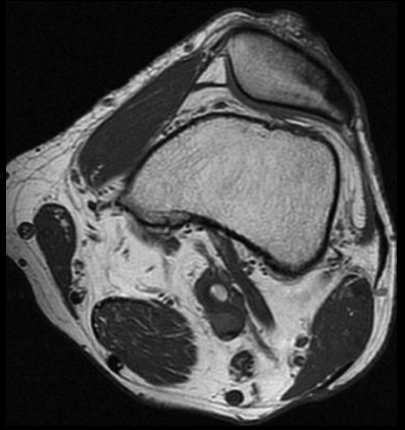

SE T1 AXIAL

3. Para confirmar los hallazgos de la angioTC de extremidades inferiores, se realizó RM de rodilla izquierda. ¿Qué hallazgo se observa en la secuencia axial SE T1?

- A. Aneurisma poplíteo trombosado.

- B. Quiste adventicial en la pared de la arteria poplítea.

- C. Banda muscular anómala rodeando a la arteria poplítea.

- D. Exóstosis de tibia comprimiendo la arteria poplítea.

- E. Flap intimal intraluminal.